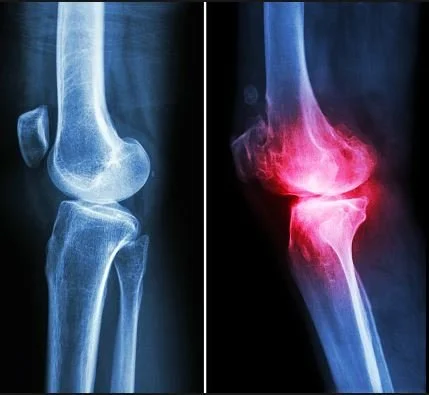

Mesenchymal progenitor cells (a specific type of stem cells) injected for the treatment of knee osteoarthritis have been in the research phase for several years. These cells can be harvested from adipose tissue present in a patient’s abdomen using a simple aspiration procedure, and prepared using a micro fragmentation system that was developed in Italy and is now available in the U.S. Dr. Peer will be using this Lipogems system initially in the operating room in conjunction with arthroscopic techniques and will be transitioning this system to use in the office for nonsurgical treatment of knee arthritis in the near future.

This injectable is a preferred treatment method for individuals still in early stages of osteoarthritis or rheumatoid arthritis. Treatments can prolong the comfort of the joint, further delaying surgical interventions. This natural substance lubricates the joints and is an already occurring substance found in the human body.

Hyaluronic acid, also called hyaluronan or hyaluronate is a gel-like substance that is naturally present throughout the human body. In the joints, natural hyaluronic acid has several functions, including: Lubrication, Growth of Cartilage and Bone, Reducing Inflammation.